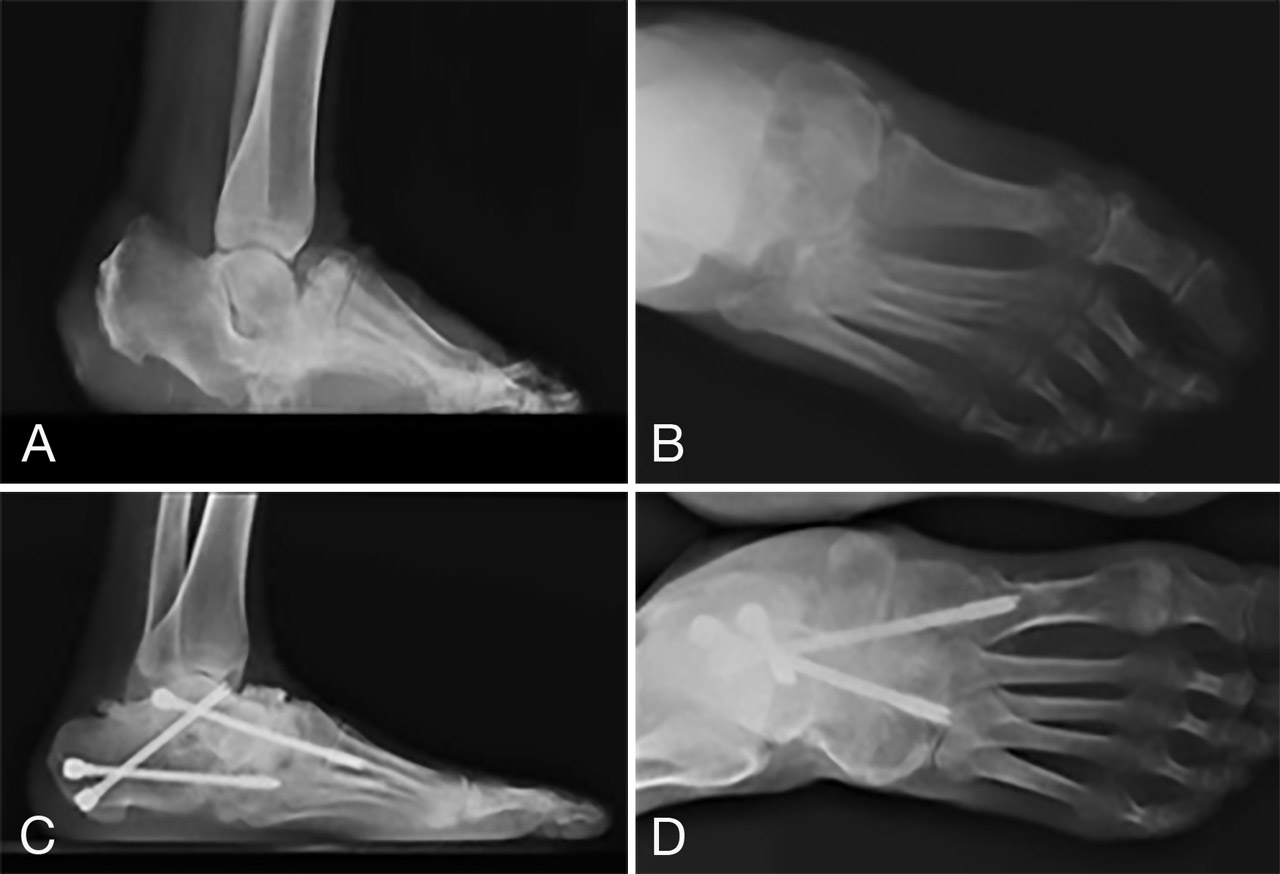

Figura 2. Paciente diabético con ulcera plantar neuropática crónica en mediopié, refractaria a tratamiento conservador, en pie convexo o “rocker-bottom”. A: Rx lateral y B: dorsoplantar con grave destrucción de articulación astrágalo-escafoidea y de Lisfranc. C: Rx lateral y D: dorsoplantar tras la reducción de la deformidad mediante osteotomía y artrodesis MIS y tenotomía MIS del tendón de Aquiles.